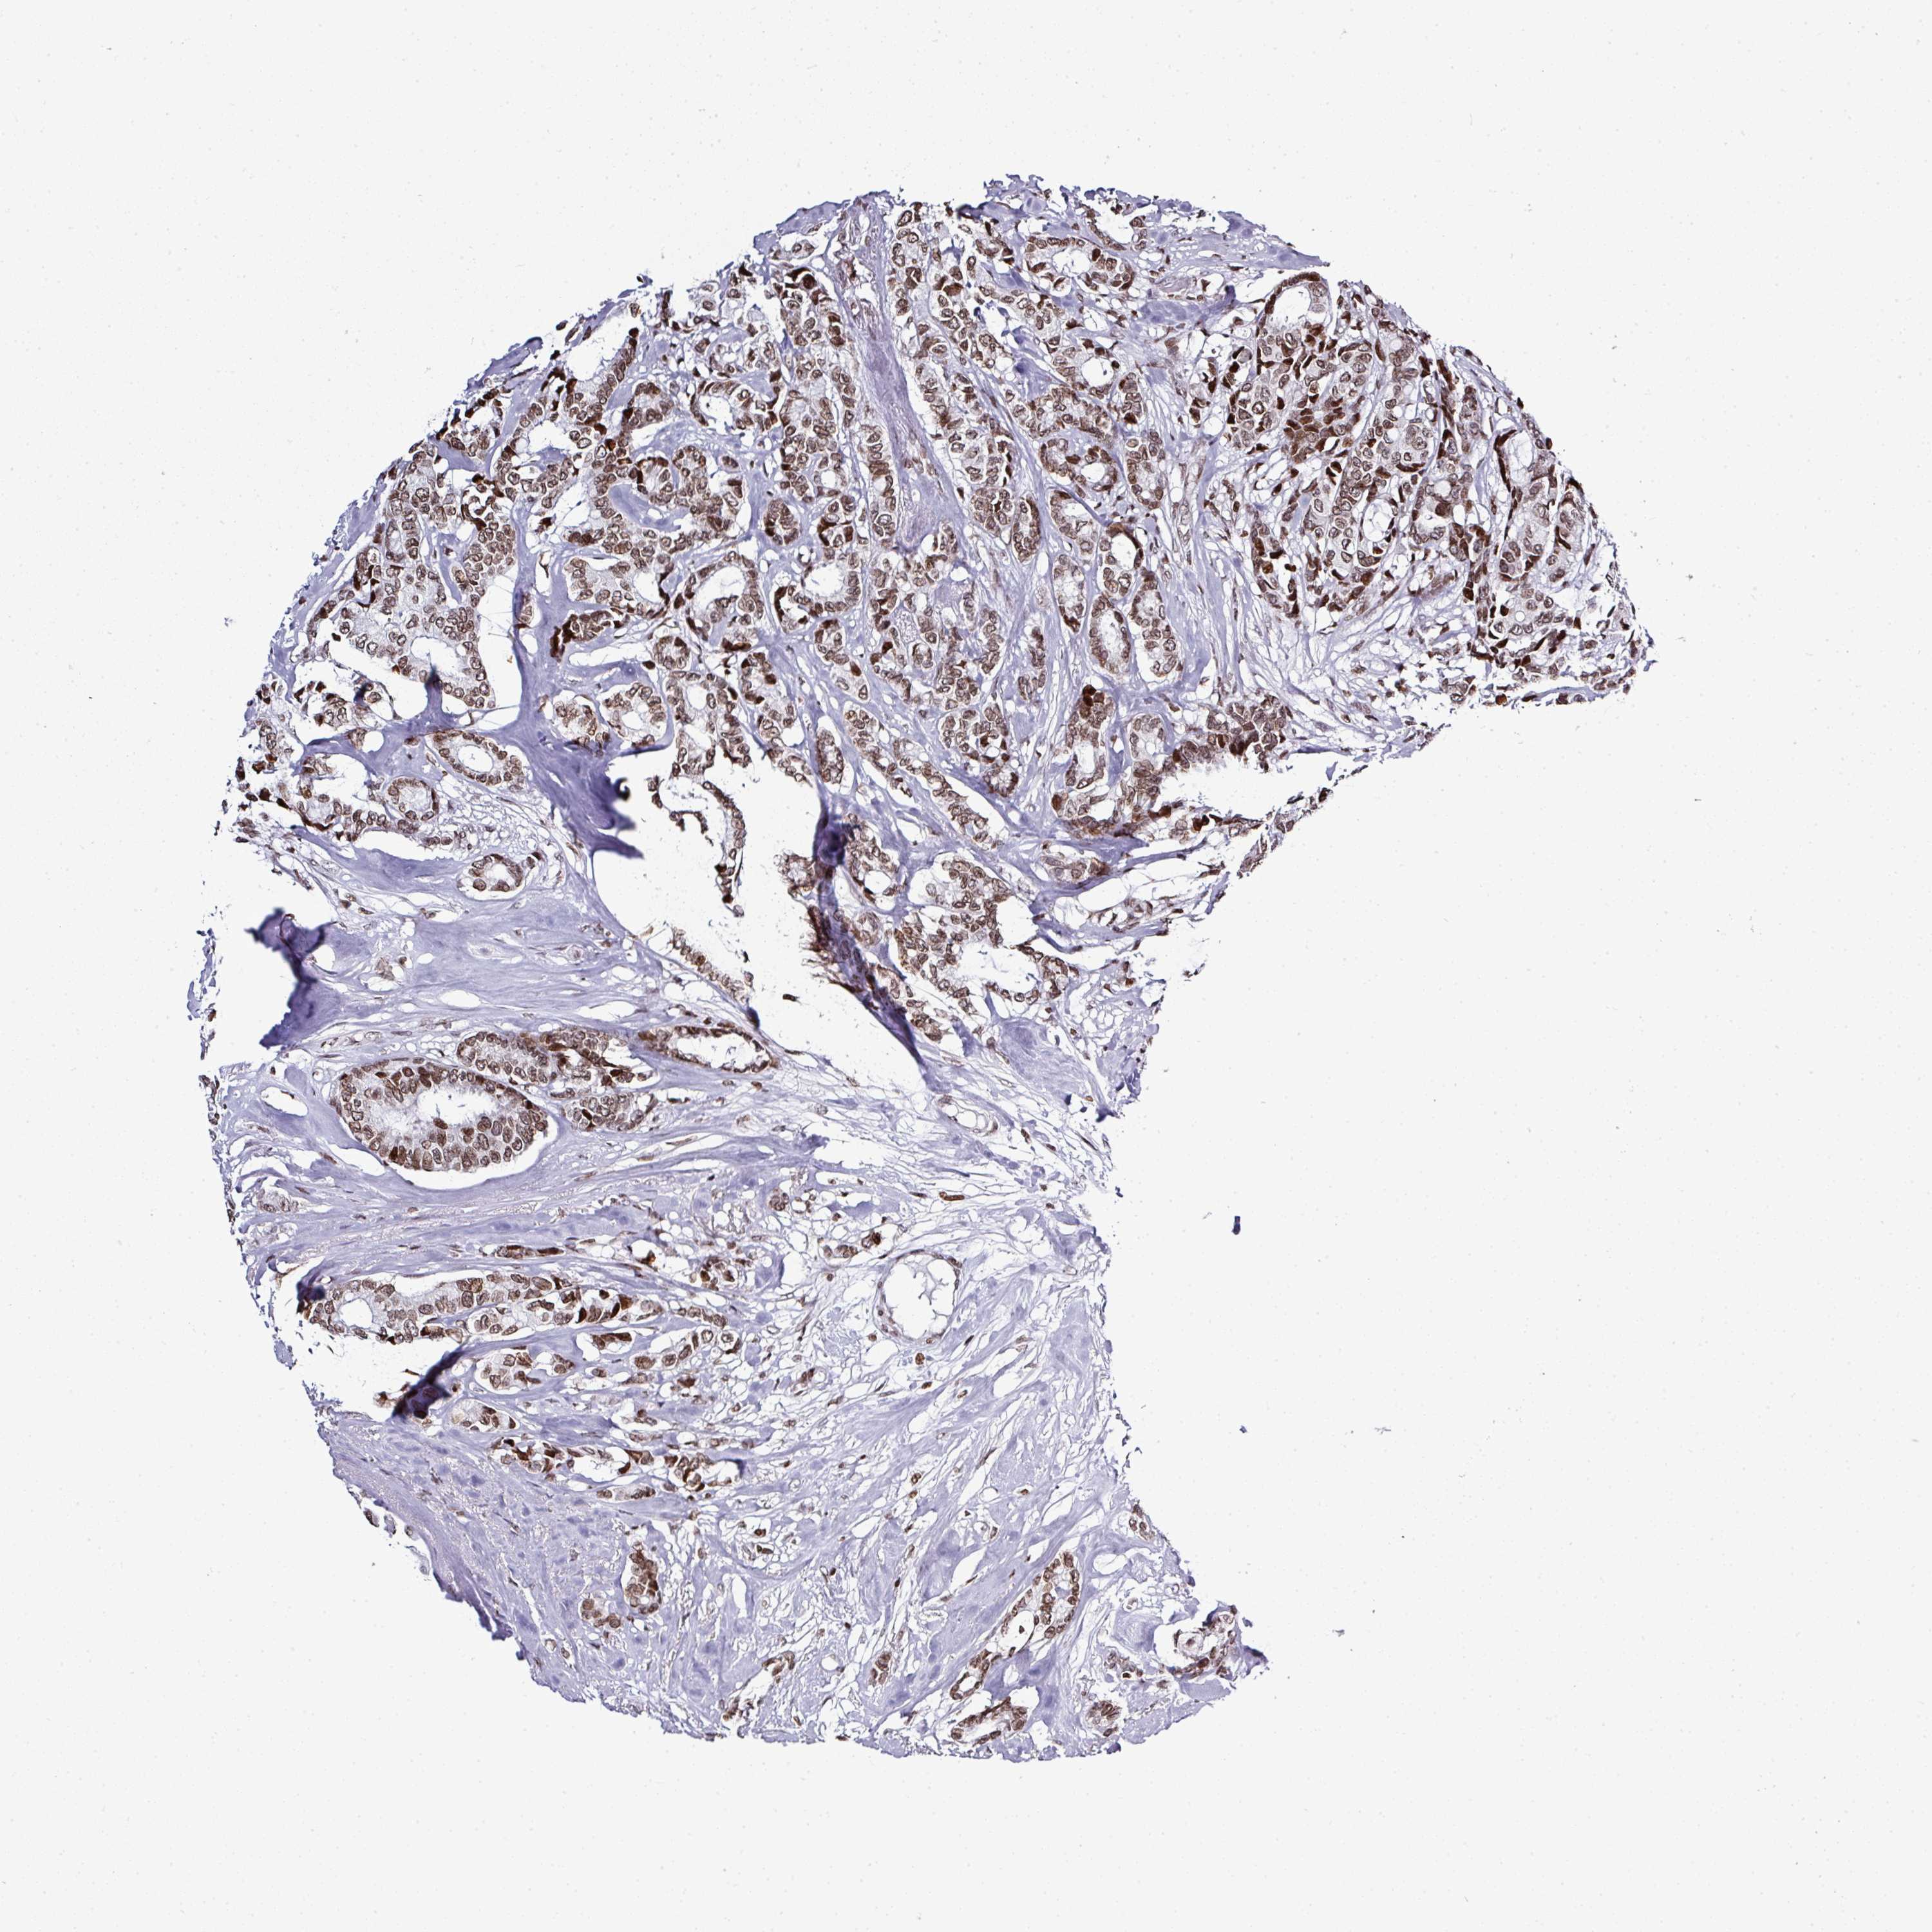

CANCER BREAST CANCER Show tissue menu

BRCA TCGA BRCA VALIDATION PROTEIN EXPRESSION

Breast cancer

Human cancer